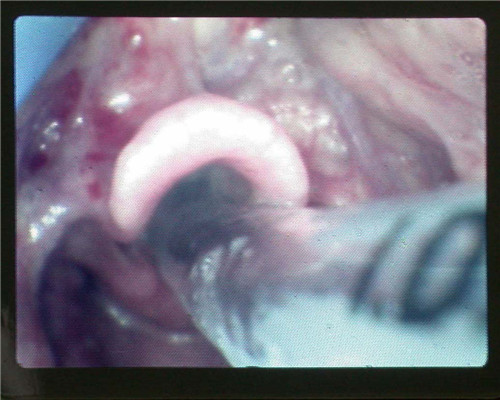

視喉鏡下的氣道開放